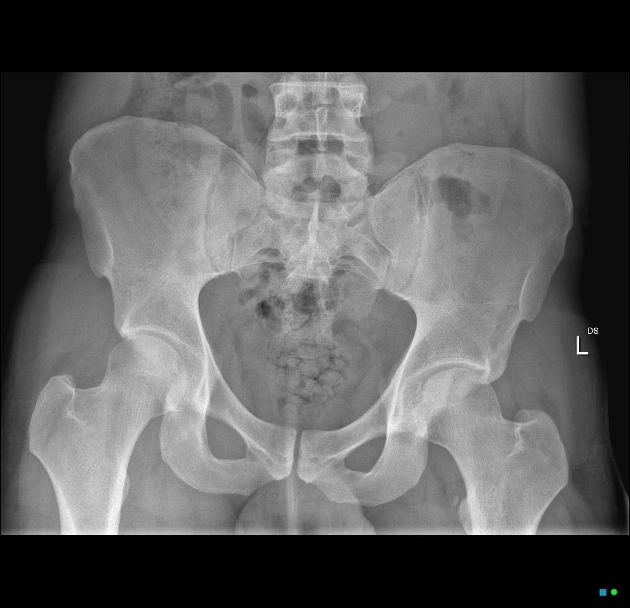

Tiếp cận X- quang xương chậu